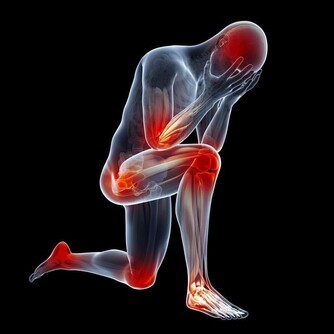

2. 非甾體抗炎藥

不少人喜歡在辦公桌上放一些像布洛芬或萘普生這樣的止痛藥。確實,當頭痛、背痛或腰痛時,這些非甾體類抗炎藥物可以讓你舒服一些。但長期服用高劑量止痛藥,不僅會出現胃腸道問題(噁心、便秘),還可能有更嚴重的並發症,如潰瘍甚至腎衰竭。當然,疼痛的時候你也沒必要硬扛著,只要嚴格按標籤服用即可。然而,如果服用超過10天,最好看醫生。